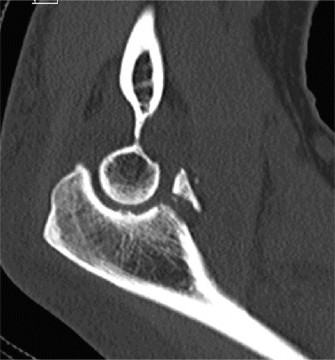

Examination reveals deformity about the elbow with no open lesions or skin tenting. He has a palpable radial and ulnar pulse and is neurologically intact. His images are shown (Figs. 2–85 to 2–88).

Figure 2–85

Figure 2–86

Figure 2–87

Figure 2–88

The correct answer is (B). This is the most common type of elbow dislocation, and often does not cause any osseous injury. Posterolateral and posteromedial dislocation account for approximately 90% of dislocations. Adequate pre- and postreduction films are necessary to evaluate for fracture, which would change the classification to a complex injury.